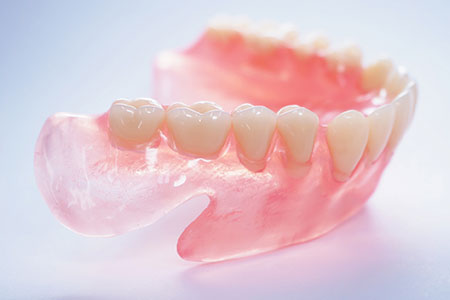

総入れ歯が合わない、痛い、噛みにくい

総入れ歯をお使いの方で、「入れ歯が痛い」「えずいて気持ち悪くなる」「硬いものが噛みにくい」といったお悩みを抱えている方は少なくありません。こうした問題は日常生活の快適さに大きく影響します。

オールオン4は、インプラントでしっかりと固定されるため、入れ歯特有の不安定さや不快感が解消され、安心して会話や食事を楽しめるようになります。